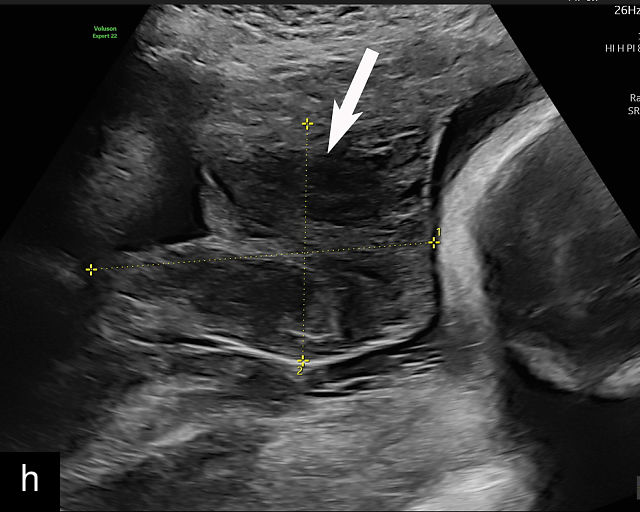

5

Placenta previa and low-lying placenta. (a) Transabdominal grayscale ultrasound image suspicious for placenta previa. The placenta (PL) appears to overlie the internal cervical os (CX). Note the time stamp: 2:19:37. (b) Transvaginal ultrasound of the same patient taken approximately 50 minutes later. Note the time stamp: 3:10:25. The internal os and the lower placental edge are both clearly seen, and the placenta does not overlie the internal os. Because the lower placental edge is 1.93 cm from the internal os, it will likely resolve by the third trimester. (c) Transabdominal grayscale ultrasound of placenta previa. The placenta (p) covers the cervix, but the cervix, especially the internal os, cannot be visualized due to shadowing. (d) Transabdominal grayscale ultrasound of placenta previa. The placenta (p) covers the cervix (c) but shadowing obscures adequate visualization. The internal os is indicated by the arrow. (e) False-positive image of placenta previa on transabdominal grayscale ultrasound. The bladder (b) is full, pushing the anterior and posterior walls of the lower uterine segment (ls) together making it appear that the placenta (p) overlies the internal os of the cervix. In reality, the line depicted by the arrowheads is where the anterior and posterior walls of the lower segment are in proximity to each other. The cervix is much lower and is obscured by shadowing (c). (f) Transabdominal grayscale ultrasound image of placenta previa. The placenta (p) covers the cervix (c), but the cervix, especially the internal os, cannot be visualized due to shadowing. b, bladder. (g) Transvaginal grayscale ultrasound image of placenta previa. The placenta (p) completely covers the internal os (arrow) of the cervix (c). The internal os can be seen clearly. h, fetal head. (h) Transvaginal grayscale ultrasound image of posterior low-lying placenta (p). The lower placental edge is clearly seen and is 1.56 cm from the internal os (arrow) of the cervix (c). The placental edge and the internal os are clearly seen. h, fetal head. (i) Transvaginal grayscale ultrasound image of a posterior placenta previa (p). The internal cervical os is clearly seen (arrow). c, cervix. (j) Transvaginal grayscale ultrasound image of an anterior placenta previa (p). The internal cervical os is clearly seen (arrow). c, cervix; h, fetal head. (k) Transvaginal grayscale ultrasound image of a posterior placenta that was thought to be low-lying on transabdominal sonography but could not be adequately assessed. This examination clearly shows the lower edge of the placenta (p) to be 2.18 cm from the internal os (arrow) of the cervix, firmly establishing that the placenta is not low-lying and allowing the patient to undergo labor safely and deliver vaginally. c, cervix. (l) Transvaginal grayscale ultrasound image of placenta previa. The placenta (p) completely covers the internal os (arrow) of the cervix (c). The internal os can be seen clearly.

This distinction is critical in determining the mode of delivery.49,51 All patients with placenta previa persisting into late pregnancy require cesarean delivery to avoid complications such as severe bleeding.50,60,61 Studies suggest that patients with a lower placental edge located more than 1 cm from the internal os may safely attempt a vaginal delivery without a significant increase in bleeding risk.68,69,70,71

Most cases of placenta previa will be suspected prenatally by transabdominal ultrasound.49 However, this approach has several limitations and may be inaccurate.72,73,74 because the relationship between the placenta and the internal cervical os may be difficult to assess by transabdominal ultrasound.72,73,74 The bladder may be full, pushing the anterior and posterior walls of the lower uterine segment together, falsely creating the impression of a placenta previa (Figure 5e).61 There may be considerable shadowing, including by the fetal presenting part, which may limit the accuracy of transabdominal ultrasound (Figure 5d,f).75 Posterior placentas may be more difficult to assess.

Transvaginal ultrasound overcomes these limitations (Figure 5g–l).72,73,74,76 The probe is inserted into the vagina and therefore is closer to the region of interest.51,61 In addition, transvaginal transducers have higher frequencies and superior resolution compared to transabdominal transducers. Transvaginal ultrasound is safe and is not associated with increased bleeding.72,73,74,75,76 As such, transvaginal ultrasound should be the imaging modality of choice whenever there is suspicion of placenta previa.49,67,77